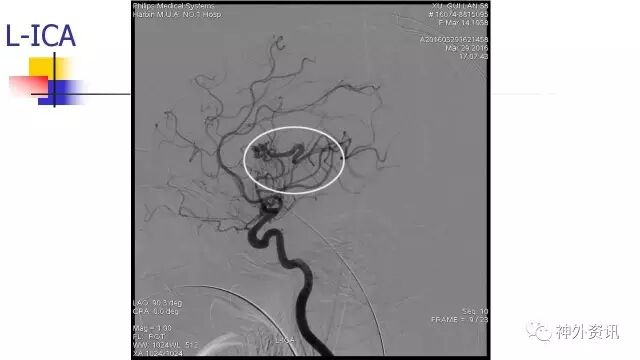

L-ICA正位动态